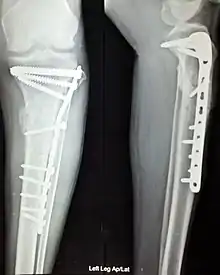

The use of intramedullary rods to treat fractures of the femur and tibia was pioneered by Gerhard Küntscher of Germany. This made a noticeable difference to the speed of recovery of injured German soldiers during World War II and led to more widespread adoption of intramedullary fixation of fractures in the rest of the world. Traction was the standard method of treating thigh bone fractures until the late 1970s, though, when the Harborview Medical Center group in Seattle popularized intramedullary fixation without opening up the fracture.

- Repair of femoral shaft fracture